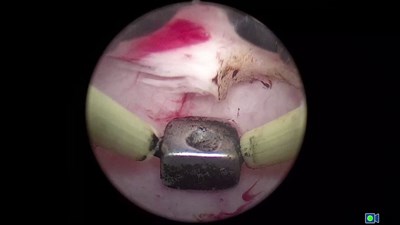

- Лазерная эн-блок резекция стенки мочевого пузыря с опухолью.

- 2018 - ЭФФЕКТИВНОСТЬ И БЕЗОПАСНОСТЬ РЕЗЕКЦИИ СТЕНКИ МОЧЕВОГО ПУЗЫРЯ С ОПУХОЛЬЮ ЕДИНЫМ БЛОКОМ С ИСПОЛЬЗОВАНИЕМ ТУЛИЕВОГО ВОЛОКОННОГО ЛАЗЕРА "УРОЛАЗ" Сорокин Н.И., Еникеев Д.В., Дымов А.М., Цариченко Д.Г., Кисляков Д.А., Гололобов Г.Ю., Севергина Л.О., Рапопорт Л.М. в журнале Онкоурология, том 14, № 1, с. 144-151 DOI

- 2018 - Лазерное удаление опухоли мочевого пузыря единым блоком Аляев Ю.Г., Рапопорт Л.М., Винаров А.З., Сорокин Н.И., Дымов А.М., Кисляков Д.А., Афанасьевская Е.В., Лекарев В.Ю. в журнале Урология, издательство Издательство Общество с ограниченной ответственностью "Бионика Медиа" (Москва), № 2, с. 147-153

- 2018 - Лазерная резекция мышечно-неинвазивных опухолей мочевого пузыря единым блоком: клинико-морфологические параллели Севергина Л.О., Сорокин Н.И., Дымов А.М., Цариченко Д.Г., Еникеев Д.В., Кисляков Д.А., Рапопорт Л.М., Коровин И.А., Королев Д.О. в журнале Онкоурология, том 14, № 3, с. 78-84 DOI

- 2020 - ТЕХНИЧЕСКИЕ АСПЕКТЫ ЛАЗЕРНОЙ EN BLOC РЕЗЕКЦИЯ СТЕНКИ МОЧЕВОГО ПУЗЫРЯ С ОПУХОЛЬЮ ПРИ МЫШЕЧНО-НЕИНВАЗИВНОМ РАКЕ МОЧЕВОГО ПУЗЫРЯ Камалов А.А., Сорокин Н.И., Дымов А.М., Кисляков Д.А., Камалов Д.М., Дзитиев В.К., Пшихачев А.М., Стригунов А.А., Афанасьевская Е.В., Тивтикян А.С., Нестерова О.Ю. в журнале Хирургическая практика, издательство Общество с ограниченной ответственностью Профиль - 2С (Москва), № 1, с. 53-58